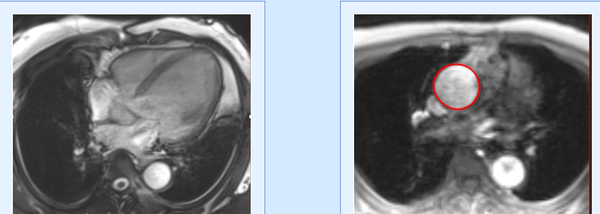

Case 226: Diagnosing Left Ventricular Free Wall Rupture without Aneurysm

Diagnosing ventricular free wall rupture is not difficult, though these patients rarely come for cardiac MRI, since they are usually serious and clinically unstable.